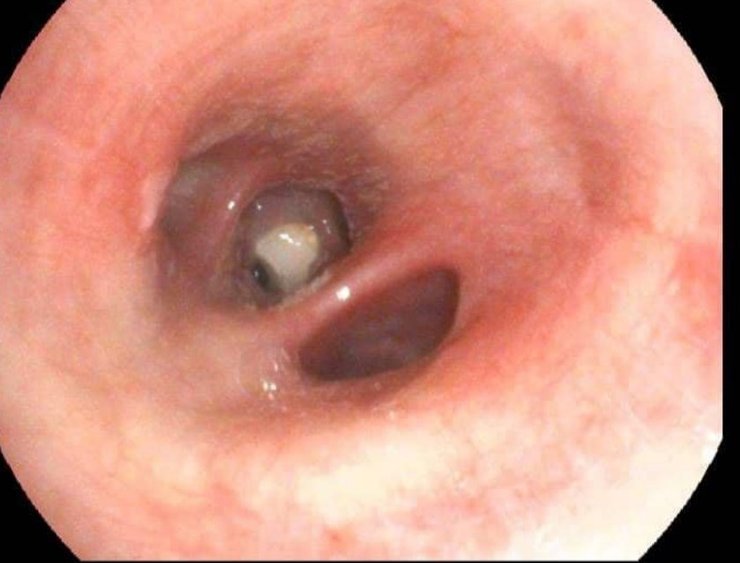

Выяснилось, что рентгенобследование ей не проводили, поскольку она кормила ребенка грудью. Женщине посоветовали обратиться за помощью к специалистам Центра легочного здоровья. Врач-пульмонолог осмотрела пациентку, а затем направила ее на рентгеноисследование. Результаты обследования и обнаружили у нее в правом нижне-щеточном бронхе часть зуба.

С помощью эндоскопической корзины специалисты Центра легочного здоровья его удалили, применив местную анестезию. Состояние женщины значительно улучшилось.